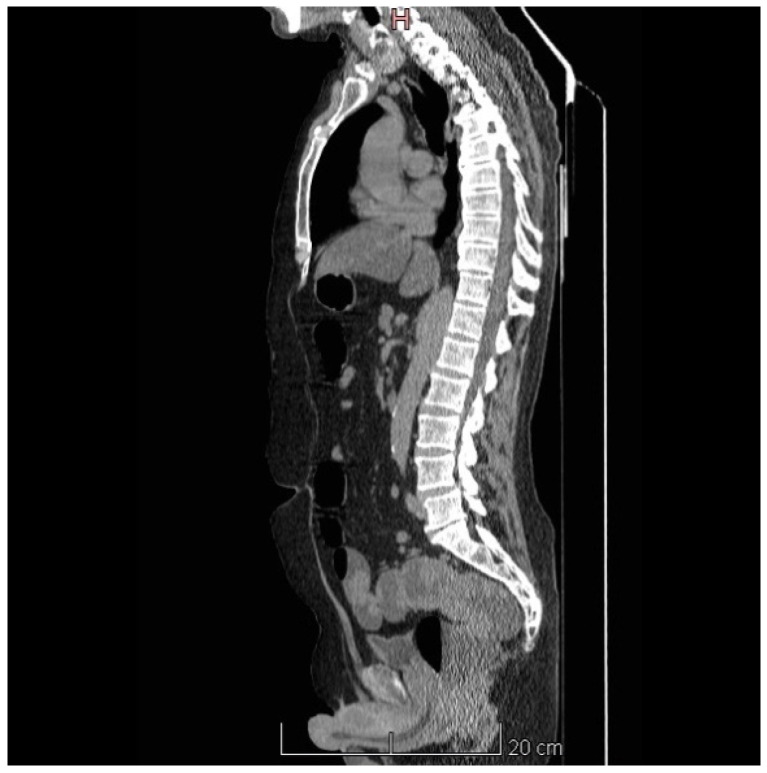

病例介绍:一名67岁男性,在数周的呕吐、虚弱和反复的晕厥发作后出现短暂的意识丧失和头晕。初步实验室结果显示低钠血症(Na 125 mEq/L)、严重低钾血症(K 2.3 mEq/L)、低氯血症(Cl 77 mEq/L)、代谢性碱血症(pH 7.5; HCO3- 34 mEq/L)、低血清渗透压(263 mOsm/L)伴尿浓度不适当(332 mOsm/kg)和肾前氮血症(肌酐3.4 mg/dL; eGFR 19 mL/min/1.73 m2;血尿素209 mg/dL)。CT增强及结肠镜检查发现直肠上部有一个大的粘液分泌绒毛状腺瘤。补充液体和电解质后,患者接受手术切除,症状完全缓解,并在随访中纠正了电解质异常。结论:直肠绒毛腺瘤应考虑在老年人不明原因的低血容量,低钾性低钠血症和代谢性碱血症。早期识别和明确切除是治疗和预防肾损伤的有效方法。

Case Presentation: A 67-year-old man presented with transient loss of consciousness and dizziness after weeks of vomiting, weakness, and recurrent syncopal episodes. Initial laboratory findings showed hyponatremia (Na 125 mEq/L), severe hypokalemia (K 2.3 mEq/L), hypochloremia (Cl 77 mEq/L), metabolic alkalemia (pH 7.5; HCO3- 34 mEq/L), low serum osmolality (263 mOsm/L) with inappropriately concentrated urine (332 mOsm/kg), and prerenal azotemia (creatinine 3.4 mg/dL; eGFR 19 mL/min/1.73 m2; blood urea 209 mg/dL). Contrast-enhanced CT, along with colonoscopy, identified a large mucus-secreting villous adenoma in the upper rectum. After fluid and electrolyte replacement, the patient underwent surgical resection with complete remission of symptoms and correction of electrolyte abnormalities on follow-up. Conclusion: Rectal villous adenomas should be considered in older adults with unexplained hypovolemia, hypokalemic hyponatremia, and metabolic alkalemia. Early recognition and definitive resection are curative and prevent kidney injury.